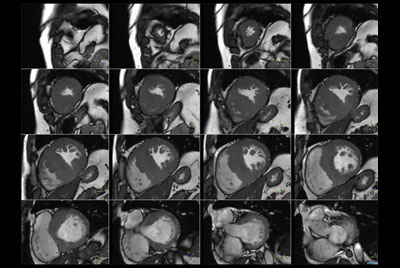

Cardiac imaging with Compressed SENSE